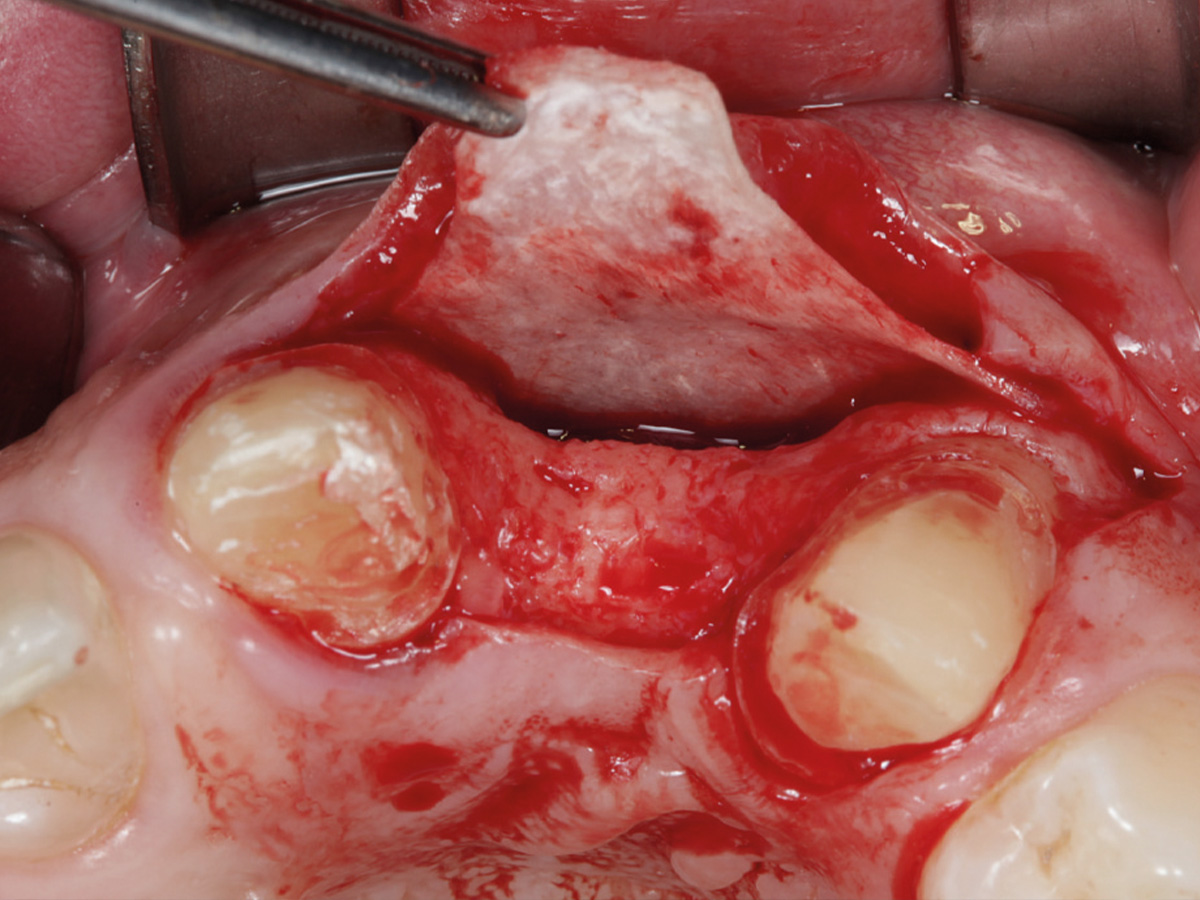

Abbildung 10

Regenerierter Bereich nach Lappenbildung. Gewebe gut durchblutet, Reste der Lamina sichtbar.